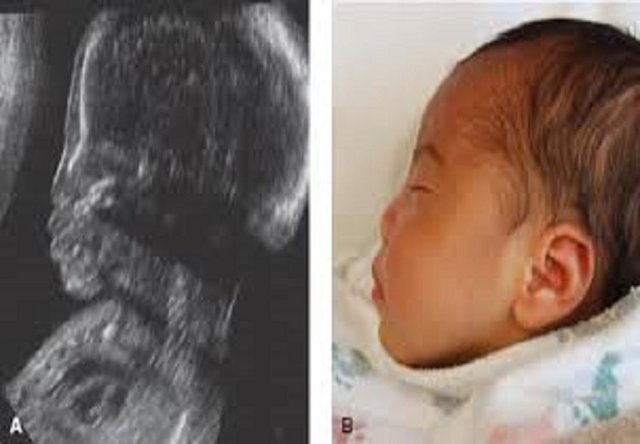

پژوهشگران آمریکایی از دانشکده پزشکی Icahn در Mount Sinai در بزرگترین پژوهشی که تا به حال برای بررسی ریسک بروز نقائص هنگام تولد، در کودکان در معرض لیتیوم انجام شده است، دریافتند ریسک ناهنجاری‌های مادرزادی عمده در جنین پس از این وضعیت در سه ماهه اول بارداری افزایش می‌یابد.

به گزارش ایسنا به نقل از The Lancet Psychiatry، کودکانی که طی سه ماهه نخست بارداری در معرض لیتیوم قرار گرفتند در مقایسه با گروه شاهد، یک و نیم برابر بیشتر به ناهنجاری‌های مادرزادی عمده دچار شدند؛ یعنی 4/7 درصد در مقایسه با 3/4 درصد. به علاوه، ریسک بستری مجدد در نوزادان در معرض لیتیوم حدودا دو برابر گروه شاهد بود؛ یعنی 5/27 درصد در مقابل 3/14 درصد. با این حال، قرار گرفتن در معرض این عنصر با عوارض بارداری یا پیامدهای زایمان، مانند پره‌اکلامپسی، زایمان زودرس، دیابت حاملگی یا وزن پایین هنگام تولد، ارتباطی نداشت.